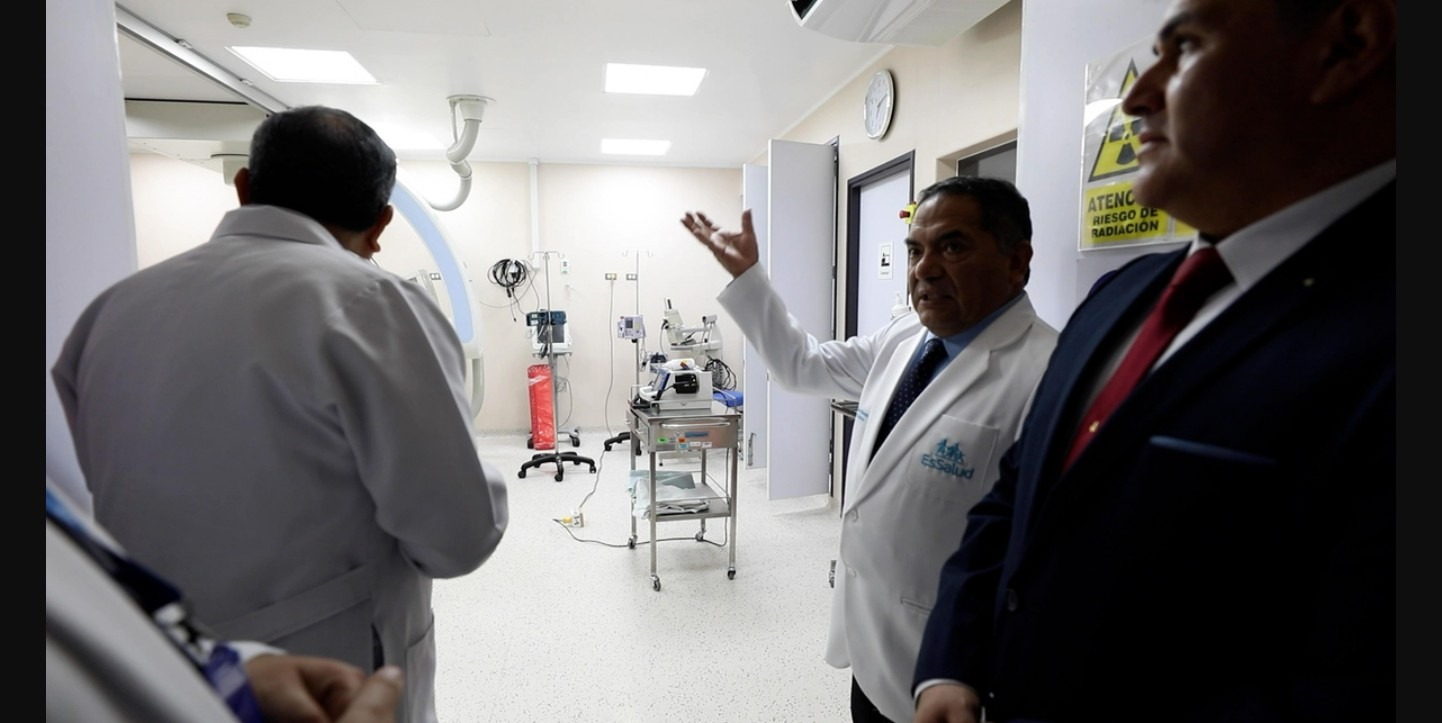

Padre de familia volverá a caminar tras cirugía de columna mínimamente invasiva en hospital Sabogal de EsSalud

Paciente llegó con fractura de columna al hospital después de un accidente en el puente de Chancay. Un equipo de experimentados neurocirujanos del Hospital Nacional Alberto Sabogal Sologuren de EsSalud logró, mediante una operación mínimamente invasiva, devolver la movilidad a un paciente con fractura de columna. El hombre, gravemente herido en el accidente del puente de Chancay, ha regresado a casa tras un mes de atención y recuperación. El presidente ejecutivo de EsSalud, doctor Segundo Acho Mego, destacó el profesionalismo y la capacidad del equipo médico, resaltando que estas cirugías son posibles gracias a la experiencia del personal de salud…